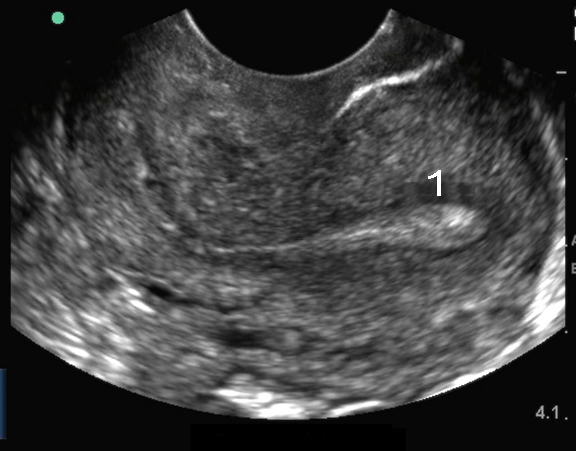

Imagen intravaginal del útero: Línea media sagital 2

Útero en retroversión

Endometrio